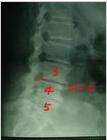

Verbiest提出在X線片上測得腰椎管中矢徑小於12mm作為診斷狹窄的標準,中矢徑在10~12mm之間為相對狹窄,小於10mm為絕對狹窄。

2.臨床症狀典型,如腰後伸受限,間歇性跛行,主訴多體徵少,CT片示矢狀徑小於12mm者。

1.明確定位 通過脊髓造影、X線片及CT片測中矢徑值,結合臨床體徵,確定椎管及根管狹窄平面。